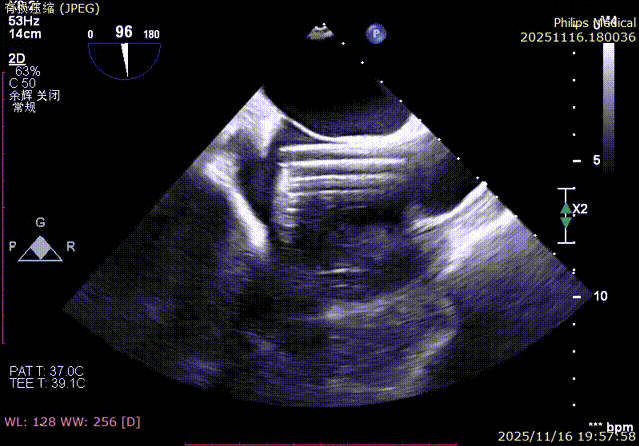

Echocardiographic Assessment: Echocardiography revealed left atrial enlargement. The left atrial appendage (LAA) orifice was 32mm with no thrombus inside. Tricuspid regurgitation was extreme (average vena contracta 18mm). Regurgitant jets were located at the anterior-septal, central, and posterior-septal commissures, with a central gap measuring approximately 13x5.9mm. The annulus was mildly dilated (average diameter 43mm). The tricuspid leaflets showed thickening and degenerative changes.

Immediate intraoperative echocardiographic verification showed that the tricuspid regurgitation area was significantly reduced from a preoperative grade of 5+(pre-op) to 2+(post-op), downgrading the severity from extreme to mild-moderate.

1.Baseline assessment of regurgitation severity.

Comparison of TR regurgitation severity: reduced from 5+ to 2+

preoperative

- TR Severity Comparison: Reduced from 5+ to 2+.